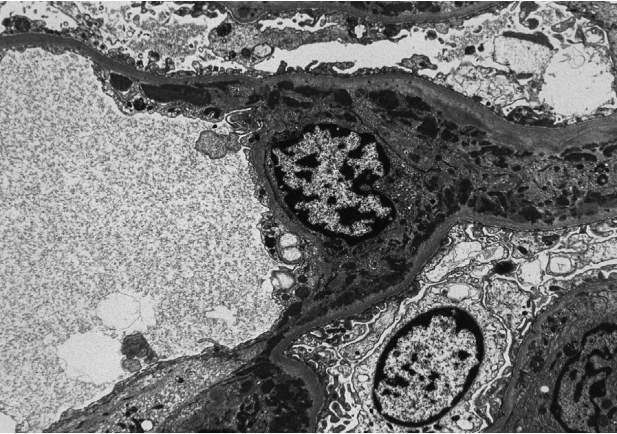

Ⅰ型和Ⅱ型存在系膜沉积,只有罕见或偶尔的上皮下或内皮下沉积。内皮细胞管网状包涵体结构。在其他狼疮足细胞病变的病例中,可能会有广泛的足突消失,与肾病性蛋白尿相关。

Ⅲ、Ⅳ型:由于系膜区、内皮下免疫复合物沉积,毛细血管内及系膜细胞增生,内皮细胞管网状包涵体结构(对高干扰素水平的反应)。可能存在分散的上皮下沉积物,涉及小于一半的肾小球和小于一半的毛细血管袢。如果大多数肾小球和毛细血管袢显示上皮下沉积,应诊断合并膜性LN(Ⅴ型)。沉积物可能表现出“指纹”样亚结构组织。

狼疮性肾炎Ⅱ型(系膜增生性LN)系膜区电子致密物的沉积(电镜)